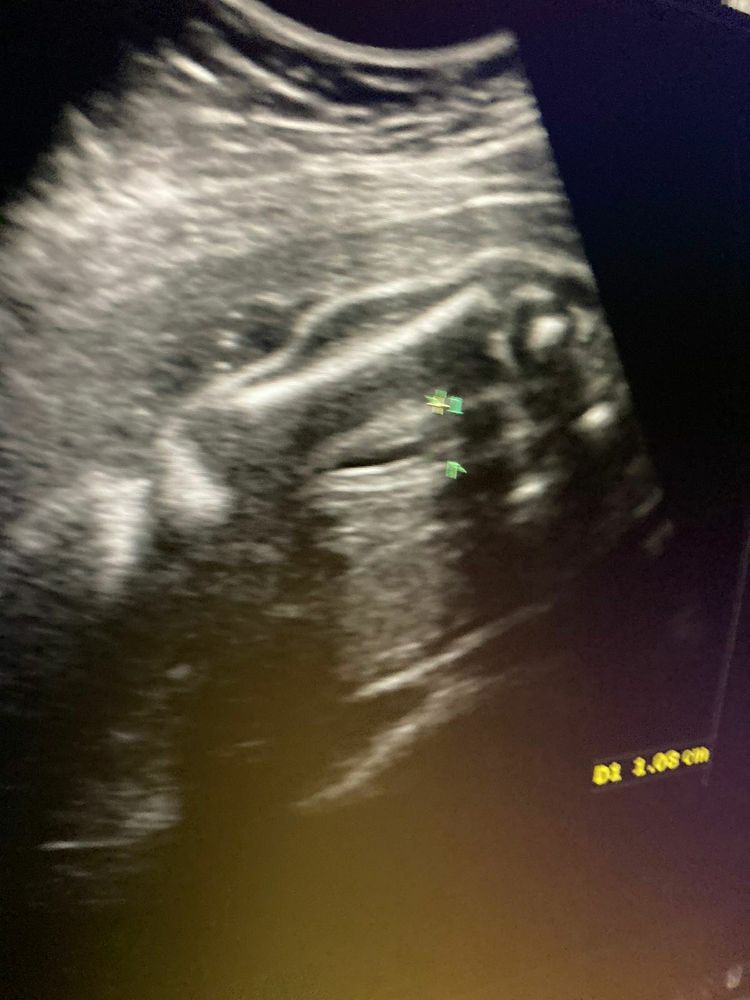

На фото зелеными стрелками отмечены половые органы.